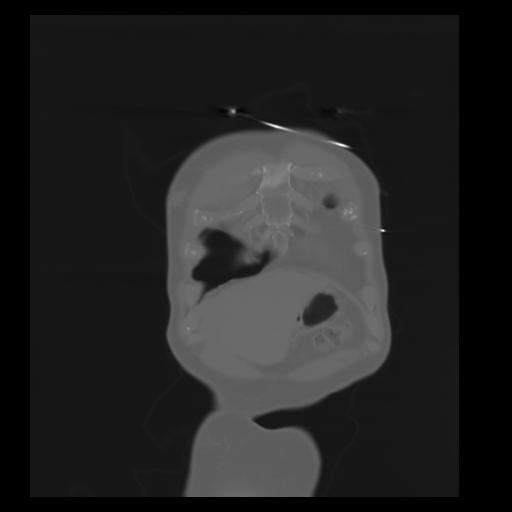

29 CUERPO,CE,Coronal,3.000,CUERPO,Coronal,